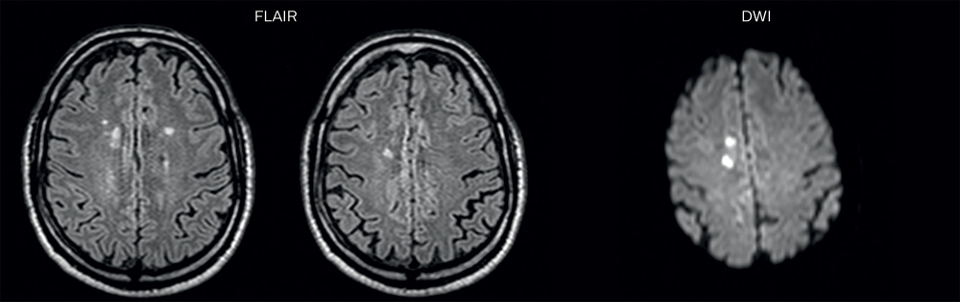

After a conventional routine MR imaging examination, the suspicion of vasculitis arose, therefore we performed an MRI including Black Blood imaging in a separate session. The dedicated ExamCard includes diffusion, FLAIR, MR angiography

using TOF, and 3D T1 MRA with bolus injection. This ExamCard also includes Black Blood imaging before and after contrast. This examination was performed on our Ingenia 3.0T. Black Blood scan time 4:39 min, acquired voxel size 0.75 x 0.75 x 1.0 mm, 21 slices.

On FLAIR images we can see some nonspecific high signal abnormalities in frontal white matter bilaterally. On DWI we can see acute ischemic lesions which appear with high signal intensity. Arrows show vessel wall enhancement which appears concentric and homogeneous in different cerebral territories.

On the routine MR sequences that we did, we could see acute

ischemic lesions. We see them very well on the diffusion images,

where acute ischemic lesions usually appear with high signal

intensity and restricted diffusion. However, the etiology of these

lesions cannot be derived from these images.